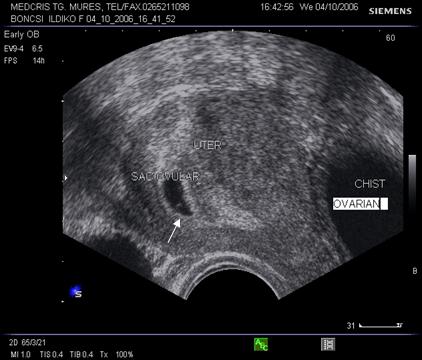

Fig nr. 8. Sarcina 5 sapt la ecografia transvaginala :sac ovular cu vezicula vitelina evidenta marcata cu sageata, retrouterin ovar chistic